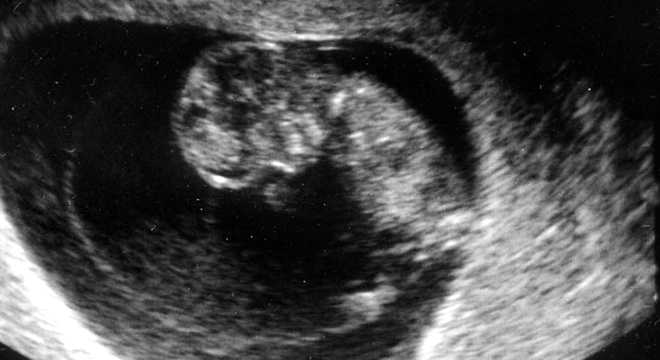

Fehlgeburt: Fötus im Uterus

Ultraschall bei Verdacht auf Fehlgeburt

Zur Diagnose einer Fehlgeburt oder einer drohenden Fehlgeburt werden verschiedene Untersuchungen und Abklärungen durchgeführt. Dazu gehören unter anderem:

• Ultraschall